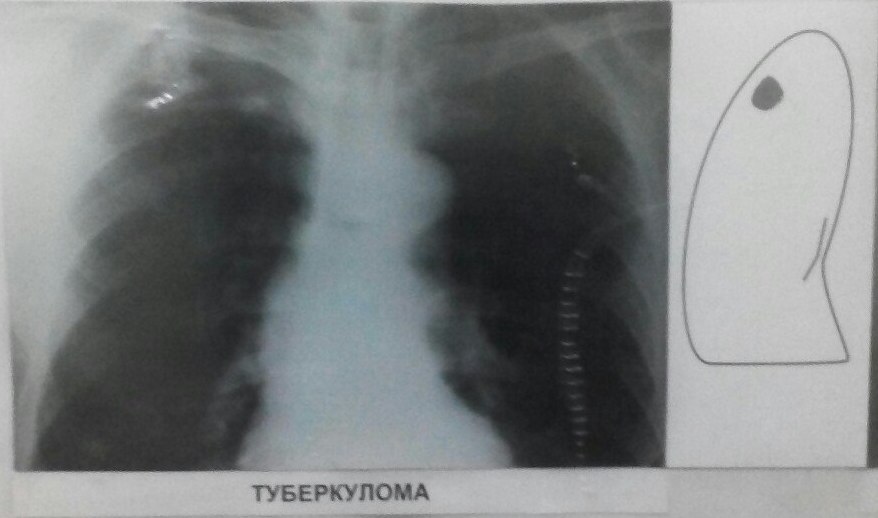

Иллюстрации по теме очагового и инфильтративного туберкулеза

Раздел: Фотодневник открытий